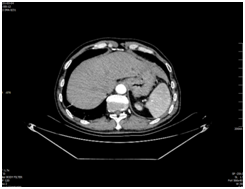

患者男性,58岁,合水县农民。术前胃镜检查、病理及胸腹增强CT检查结果综合提示,诊断为进展期胃癌(cT3N2M0)。

(术前腹部增强CT显示:胃底部胃壁增厚强化)